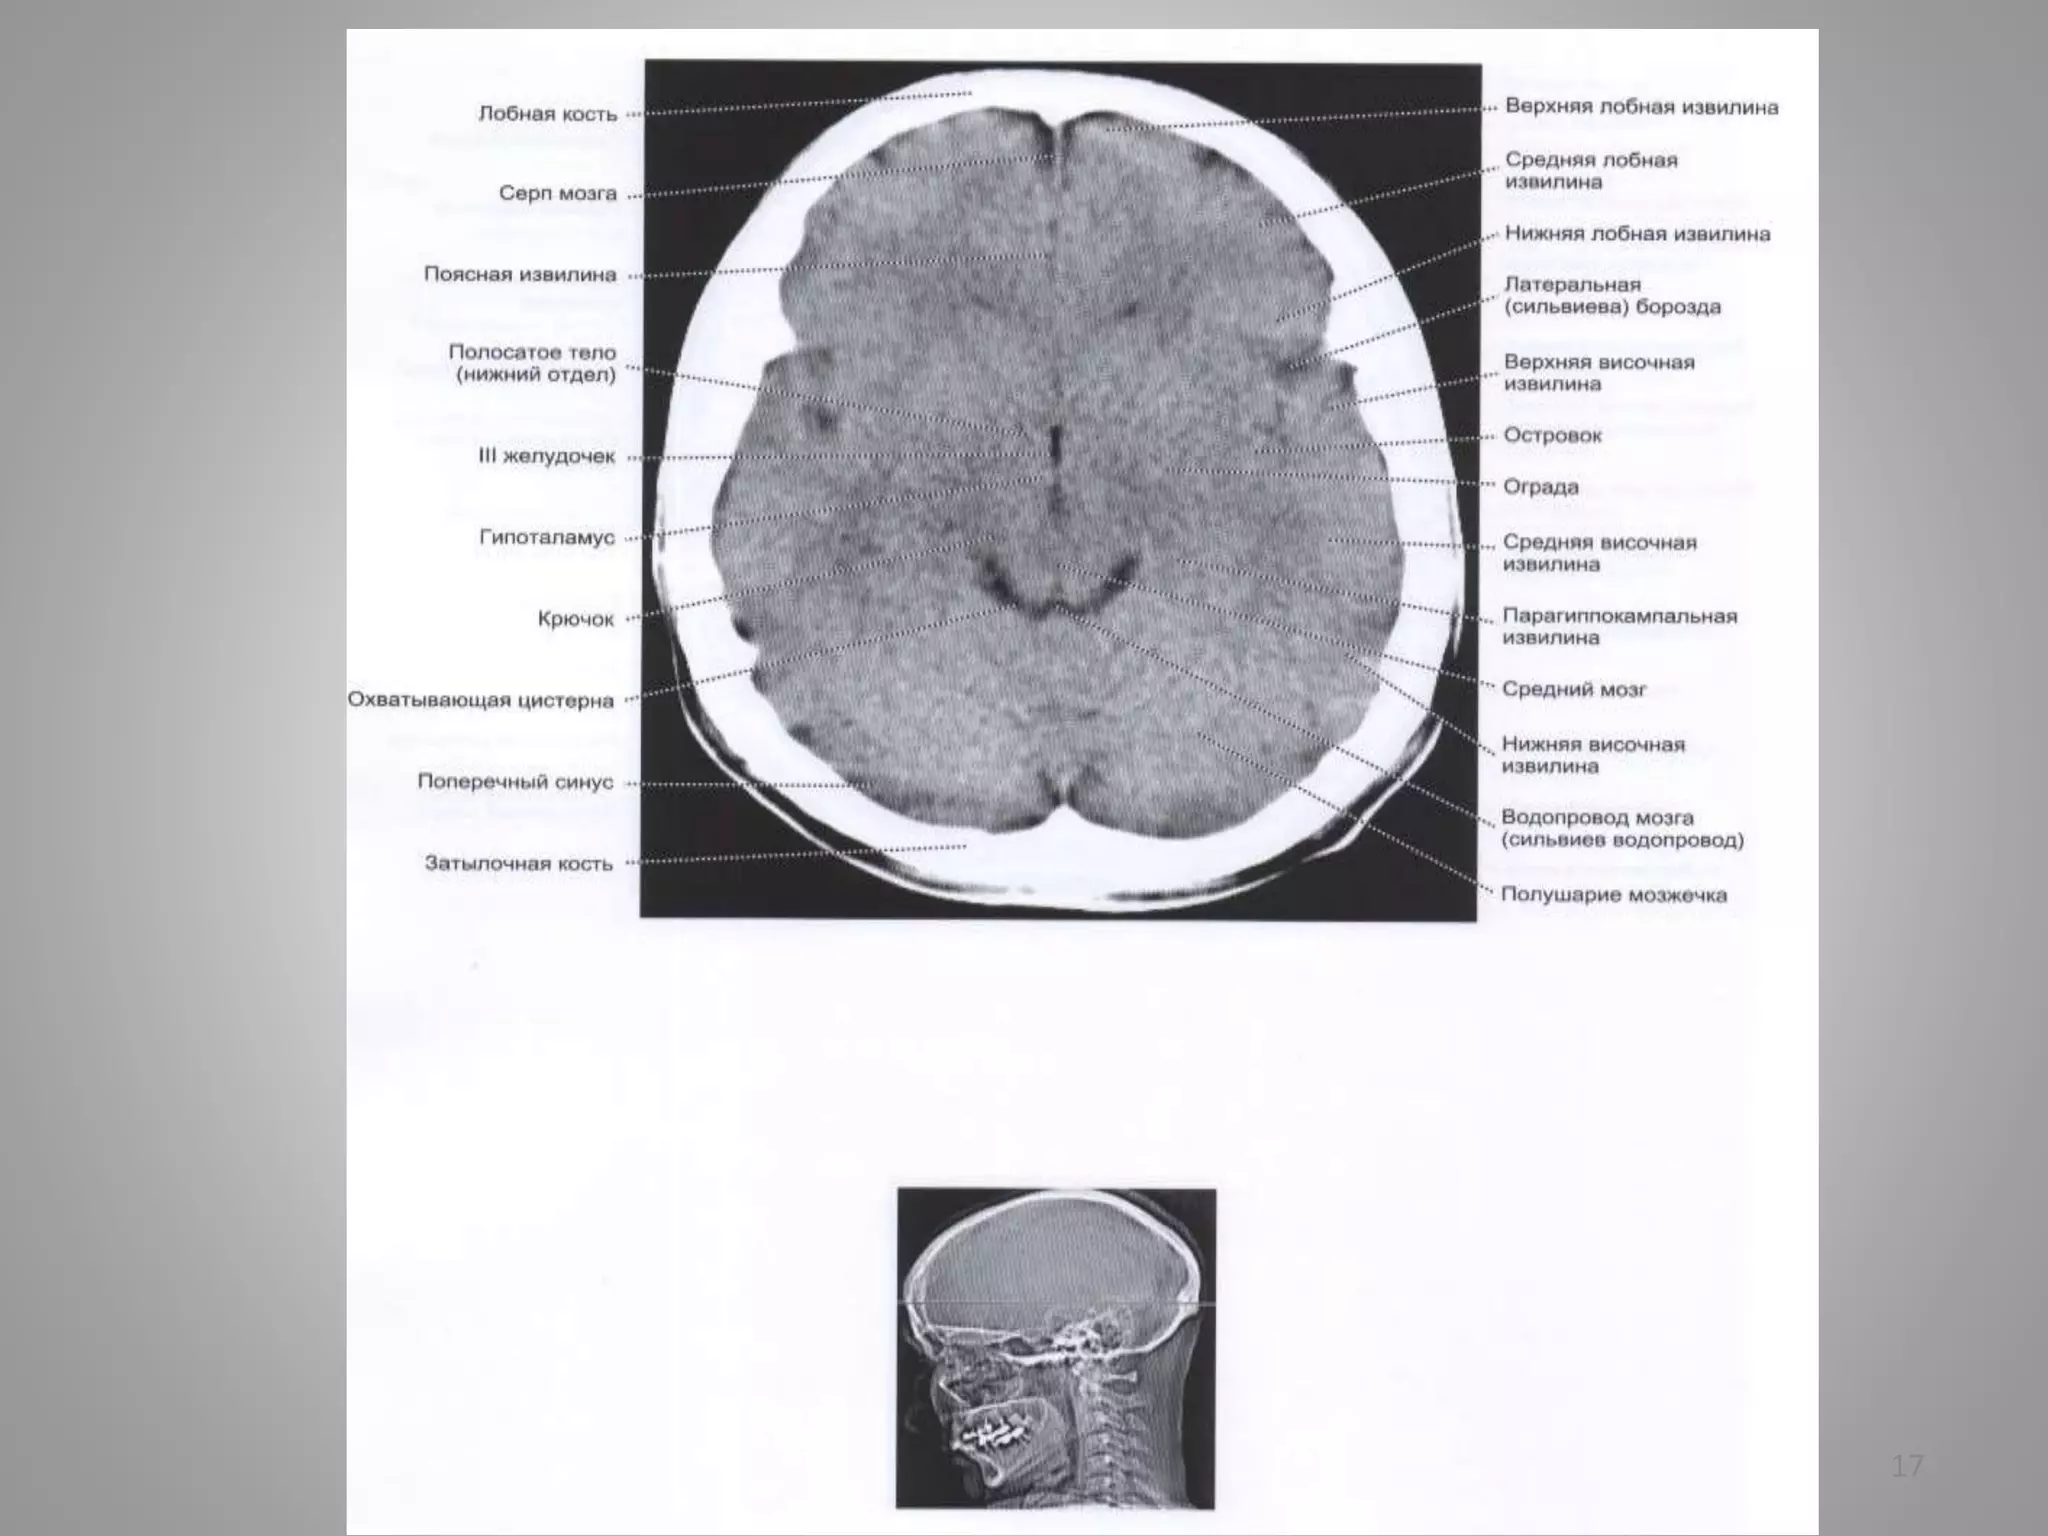

Деякі особливості КТ

79